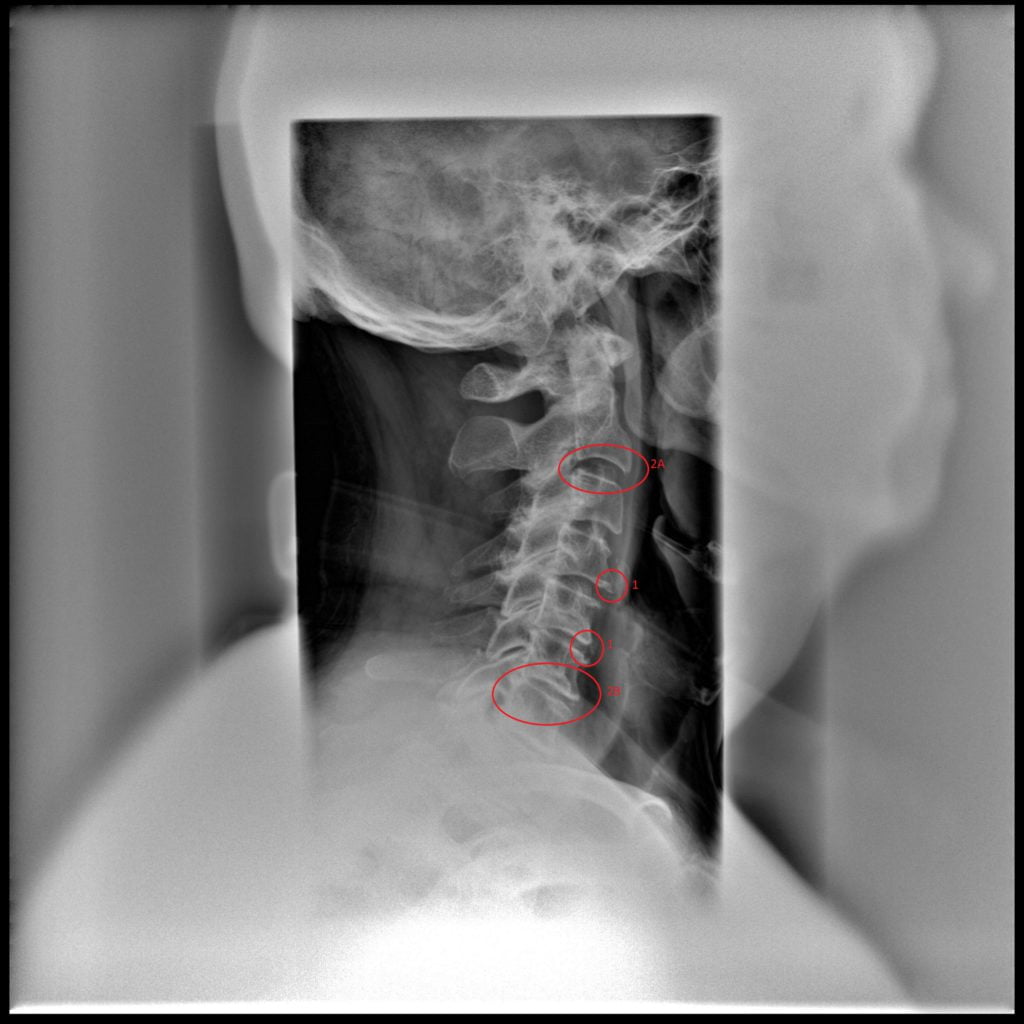

Рентген поясницы: анатомические особенности и медицинские исследования